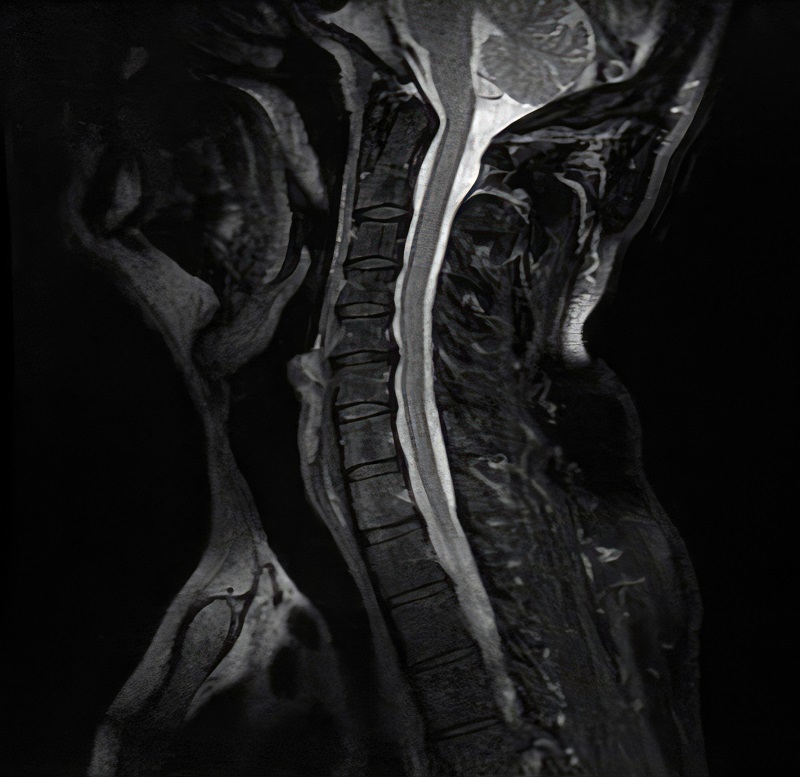

MRI and Ultrasound Data - Endometriosis

AI-driven project supporting early and non-invasive detection of endometriosis. BulletProve develops advanced diagnostic tools that analyze multimodal medical data to identify patterns associated with the disease.

- Analysis of imaging data such as MRI and ultrasound (USG)

MRI and ultrasound data analysis for endometriosis